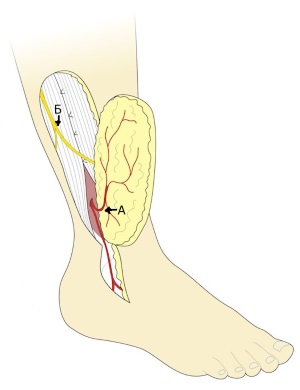

Рис. 5. Ротированный лоскут. Этот тип лоскута кровоснабжается антеградным кровотоком от перфорантной ветви малоберцовой артерии. В рассечение кожи над латеральной лодыжкой нет необходимости, если точкой ротации (pivot point) лоскута является перфорантная артерия (А- кожная ветвь в лоскуте; Б – поверхностный малоберцовый нерв).

Сосудистая ножка формируется за счет дистального фрагмента малоберцовой артерии, которая проходит кпереди от лодыжки на стопу. В этом варианте формирования лоскута его кровоснабжение обеспечивается за счет ретроградного тока от дистальных анастомозов артерии. Ножка может быть выделена дистально до анастомозов с латеральной предплюсневой артерией на уровне пазухи предплюсны (рис. 6) [5].

Рис. 6. Островковый надлодыжечный лоскут на дистальном основании.

А- Лигированная перфорантная ветвь малоберцовой артерии, Б- Восходящая кожная ветвь в составе лоскута, В- Нисходящая ветвь

В некоторых случаях возможно продолжение дессекции до уровня бугристости пятой плюсневой кости. Перфорантная ветвь малоберцовой артерии легируется как можно глубже места отхождения кожной ветви к лоскуту. Для выполнения этого легирования может потребоваться создание небольшого раскрытия межкостной перегородки с целью лучшей визуализации малоберцовой артерии. Выделение сосудистой ножки до синуса предплюсны на 8 см. в длину дает возможность обеспечить большую дугу ротации для латерального надлодыжечного лоскута (Рис. 6Г). Дистальная ножка всегда сопровождается одной или двумя крупными венами, которые обеспечивают венозный отток.